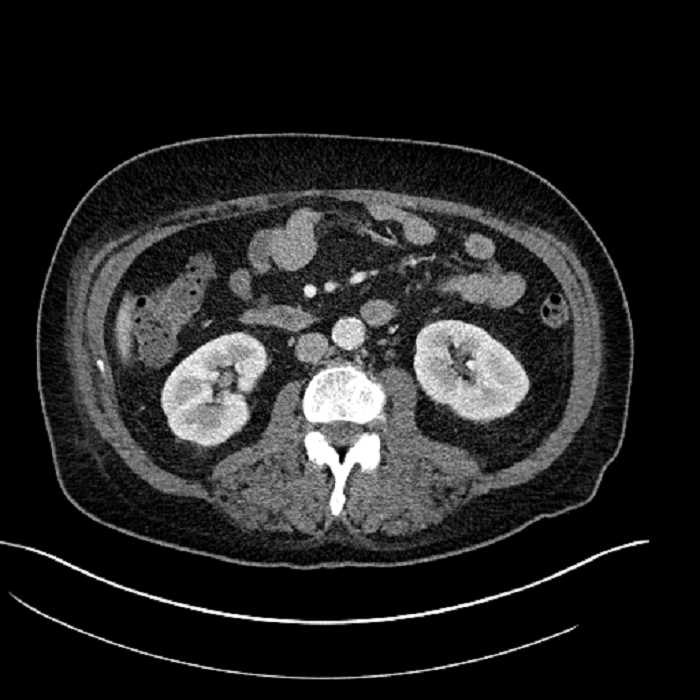

Age: 63

Sex: Male

Indication: Abdominal pain

• Large fluid density structure in hepatic segments 7 and 8 measuring 10 x 7 x 7 cm with internal septation and circumferential ill-defined low density compatible with edema

• Clearly marginated fluid density structure in segment 7 and several other scattered tiny hypodensities, which likely represent cysts

• Hepatic abscess

Acute sigmoid diverticulitis complicated by a small contained perforation and a large abscess in the right hepatic lobe. Additional small subcapsular abscesses along the anterior margin of the left hepatic lobe.

• The classic CT imaging appearance is a double target sign with internal low density surrounded by an internal enhancing rim (capsule) and a low density external rim (edema)

Hepatic abscess showing the double target sign with low density internally surrounded by a thin inner enhancing rim (red arrow) and ill-defined outer low density rim (yellow arrow). Blue arrow indicates an internal septation. Red arrows: additional smaller subcapsular abscesses. Red arrow: focal contained perforation associated with diverticulitis.